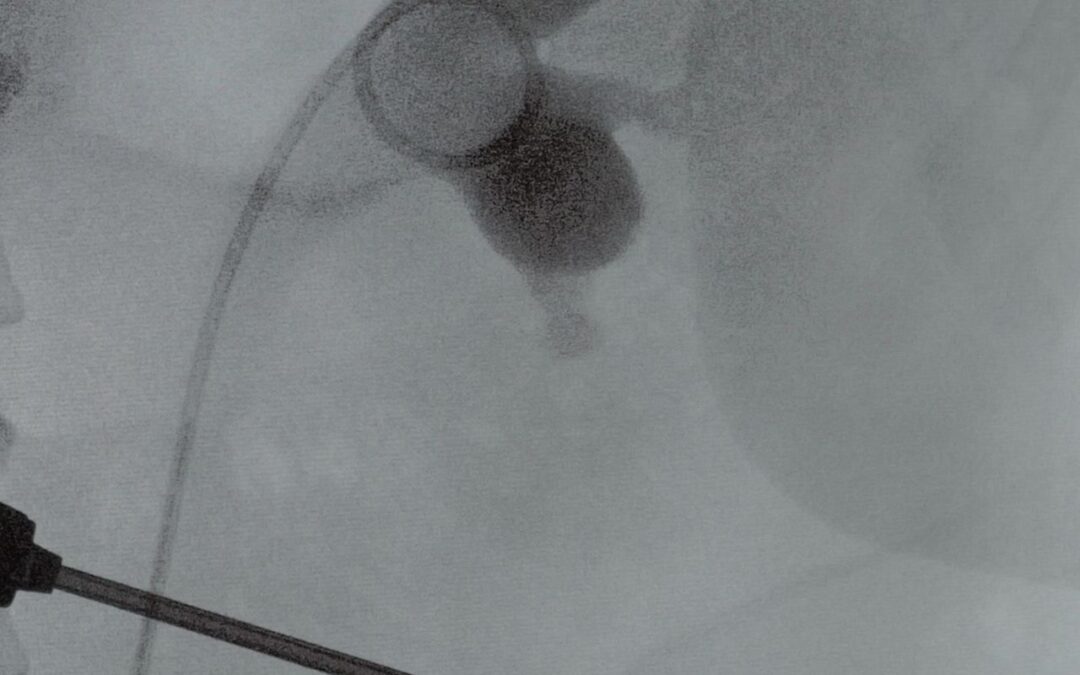

- Introduction d’un cystoscope par l’urètre.

- Visualisation de l’orifice urétéral.

- Progression d’un guide dans l’uretère.

- Mise en place de la sonde.

Durée de la Procédure

La procédure est mini-invasive, dure généralement entre 15 et 30 minutes et ne nécessite pas d’incision chirurgicale.